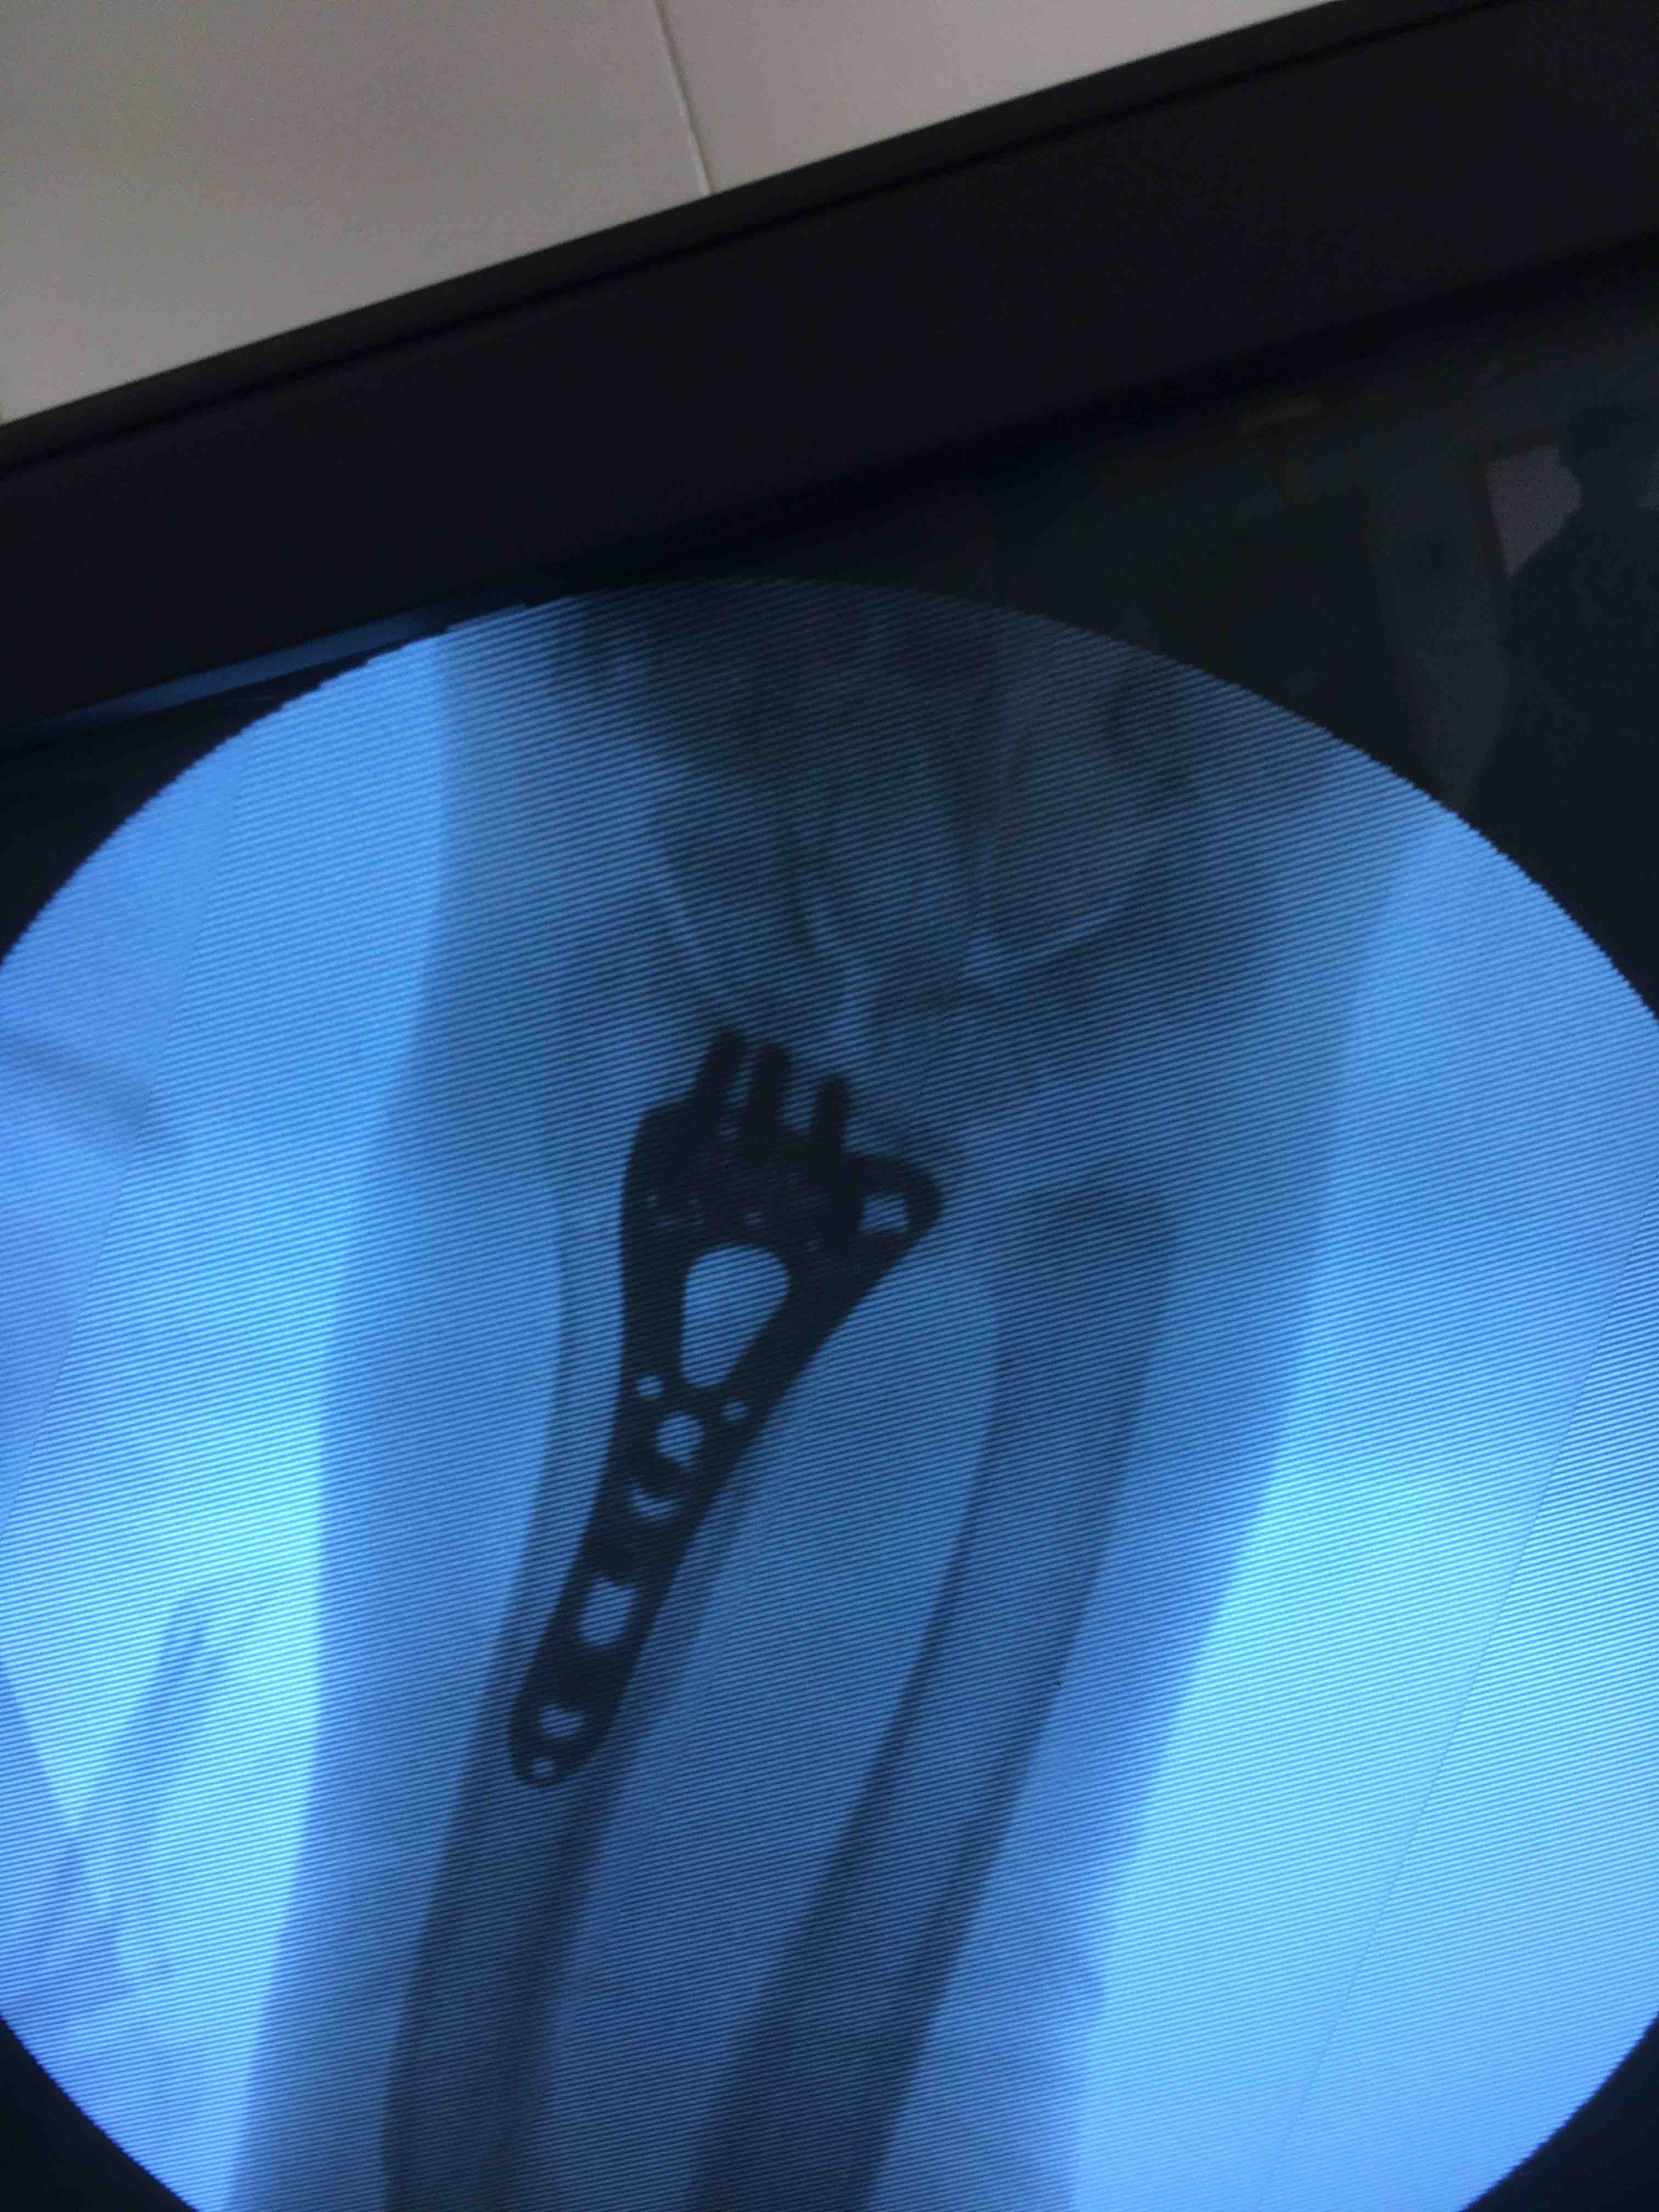

打开应用老年患者colles骨折(切复内固定术)

在臂丛麻醉下行切复内固定术,术后抗炎对症处理。